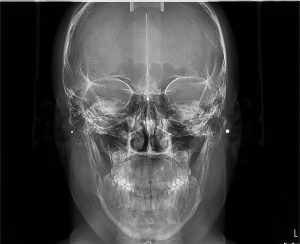

3. ΟΠΙΣΘΟΠΡΟΣΘΙΑ ΚΕΦΑΛΟΜΕΤΡΙΚΗ ΑΚΤΙΝΟΓΡΑΦΙΑ

Η οπισθοπρόσθια ακτινογραφία είναι μια κατά μέτωπο ακτινογραφία του κρανίου.

Δίνει τη δυνατότητα αξιολόγησης πιθανής ασυμμετρίας μεταξύ του δεξιού και αριστερού ημιμορίου της άνω και κάτω γνάθου. Επίσης με αυτήν απεικονίζονται και αξιολογούνται οστικά κατάγματα της κάτω γνάθου που μπορεί να εντοπίζονται στο σώμα, τον κλάδο ή τη γωνία αυτής.

Η λήψη της είναι γρήγορη (διαρκεί λίγα δευτερόλεπτα) και ανώδυνη.